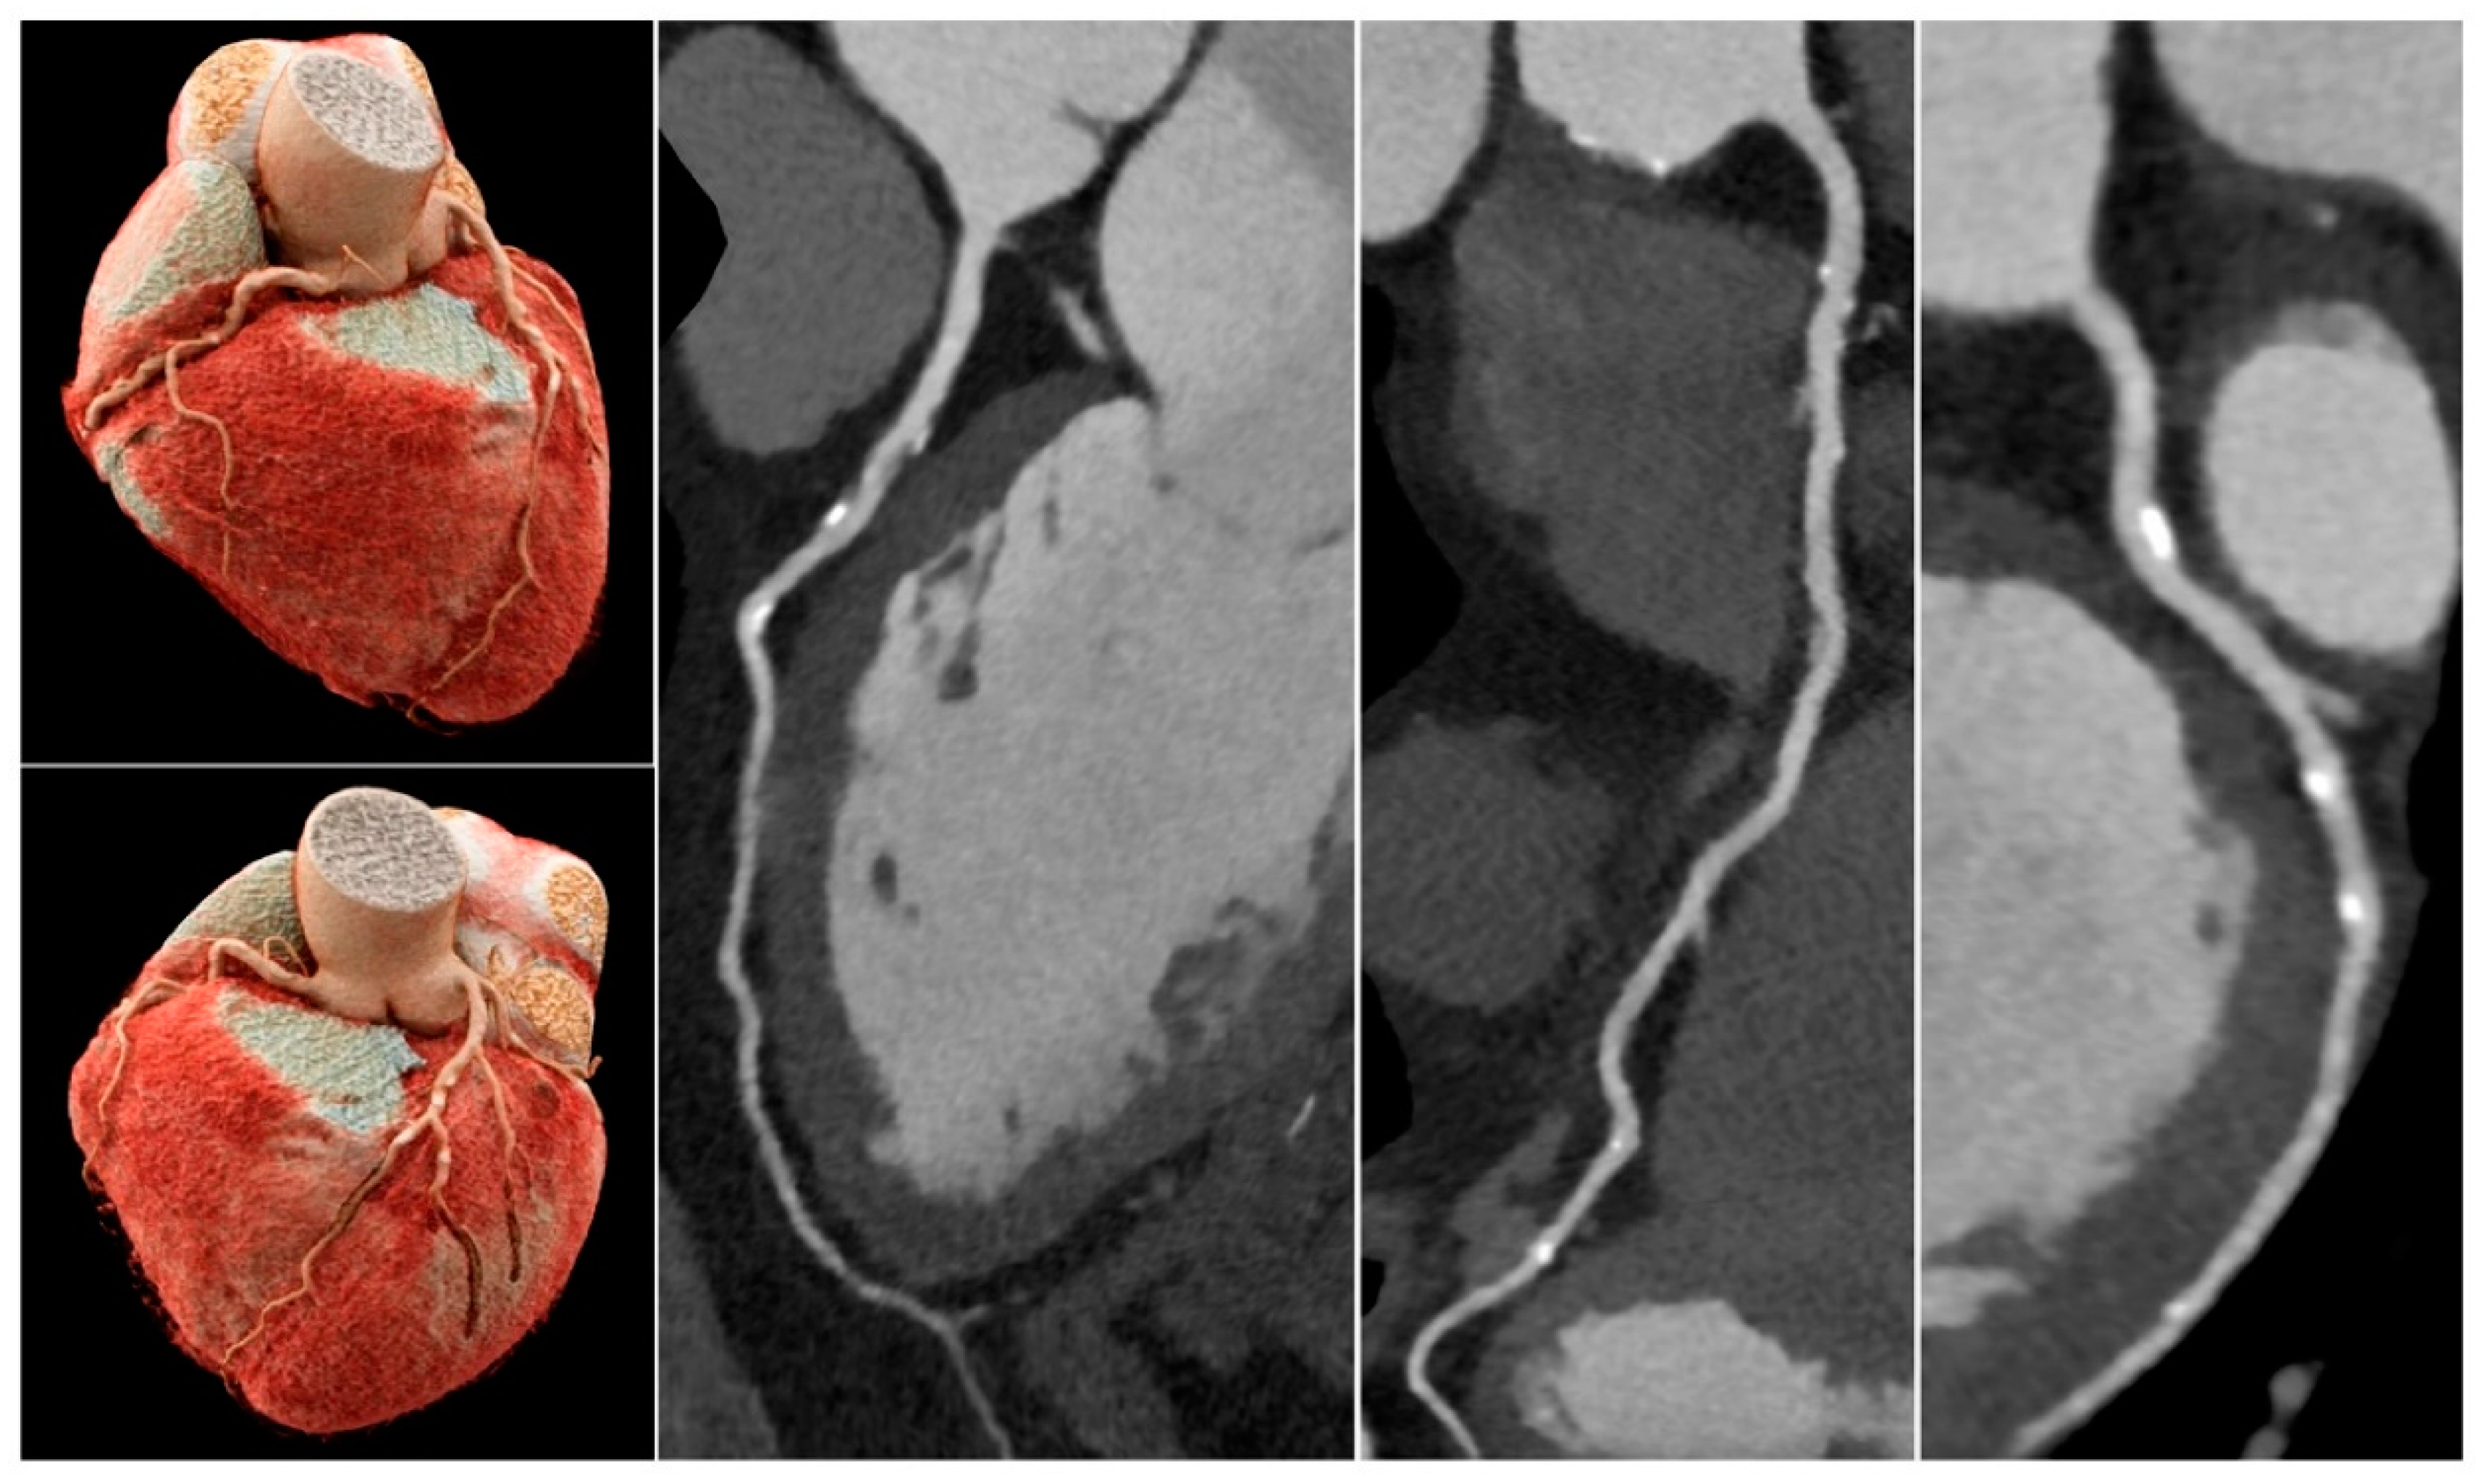

Although it is currently impossible to use micro-CT in patient imaging, findings of this study highlight the importance of using high-resolution imaging for the improvement of assessing calcified coronary plaques and a reduction in false positive rates. Compared to the current medical CT scanners with 0.5x0.5x0.5 mm spatial resolution, photon-counting CT represents the latest technological advancement with ultra-high resolution of 0.2 mm, excellent image quality and further reduction in blooming artifact caused by the severe calcification or coronary stents [45,46,47,48,49]. Recent studies based on phantom experiments showed that photon-counting CT has improved quantification of coronary stenosis with reduced blooming artifact, independent of heart rates when compared to the standard CCTA (0.2 mm vs 0.4 mm slice thickness) [45,46]. This is also confirmed by patient studies using the photon-counting CT. Si-Mohamed et al. reported their initial experience with photon-counting CT in patients with 100% improvement in overall image quality in calcification [47]. Hagar et al. analyzed imaging of 68 patients showing that photon-counting CT had 96% sensitivity, 84% specificity and 88% accuracy in the assessment of significant CAD. Even in patients with severe calcification (Agatston score of at least 1000), photon-counting CT still had a high performance with 93% sensitivity, 70% specificity and 83% accuracy [48]. Soschynski et al. in their multi-center study consisting of 92 patients further validated these findings with a high diagnostic performance: 92% sensitivity, 96% specificity and 95% accuracy (Figure 9) [49]. Photon-counting CT is likely to make significant contributions to the improvement of diagnostic assessment of calcified coronary plaques in future.

Figure 9. Coronary computed tomography angiography images of a 75-year-old male patient with atypical angina pectoris. Total Agatston score was 589. All coronary segments were diagnostic. Despite a high plaque burden, all calcified plaques were assessable with <50% stenosis and hence significant coronary stenosis could be excluded with high certainty. Reprint from Soschynski et al. with permission under open access Creative Commons CC BY 4.0 license [49].